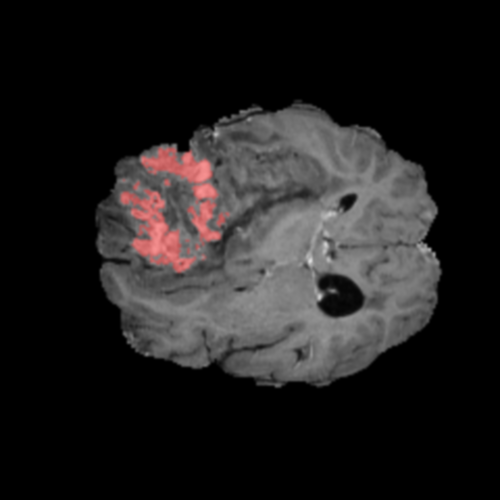

Mapas de Explicabilidad (Grad-CAM++)

Visualización de las regiones de atención del modelo que validan su razonamiento clínicamente relevante

Ejemplos HGG - Atención en Núcleo Necrótico y Tumor Realzado

HGG Grad-CAM++ 1 HGG Grad-CAM++ 2 HGG Grad-CAM++ 3 HGG Grad-CAM++ 4 HGG Grad-CAM++ 5 HGG Grad-CAM++ 6

Los heatmaps muestran que el modelo concentra su atención en las regiones de Tumor Realzado (rojo) y Núcleo Necrótico (azul), características patológicas clave de los gliomas de alto grado.

Validación con IA Explicable

El análisis Grad-CAM++ reveló que el modelo desarrolla automáticamente la capacidad de localizar las regiones tumorales. Para casos HGG, la atención se alinea fuertemente con las regiones de Tumor Realzado (ET) y Núcleo Necrótico (NCR). En contraste, los casos LGG muestran atención más difusa, principalmente concentrada en la región de Edema Peritumoral (ED), lo cual es consistente con la patofisiología conocida de los gliomas.